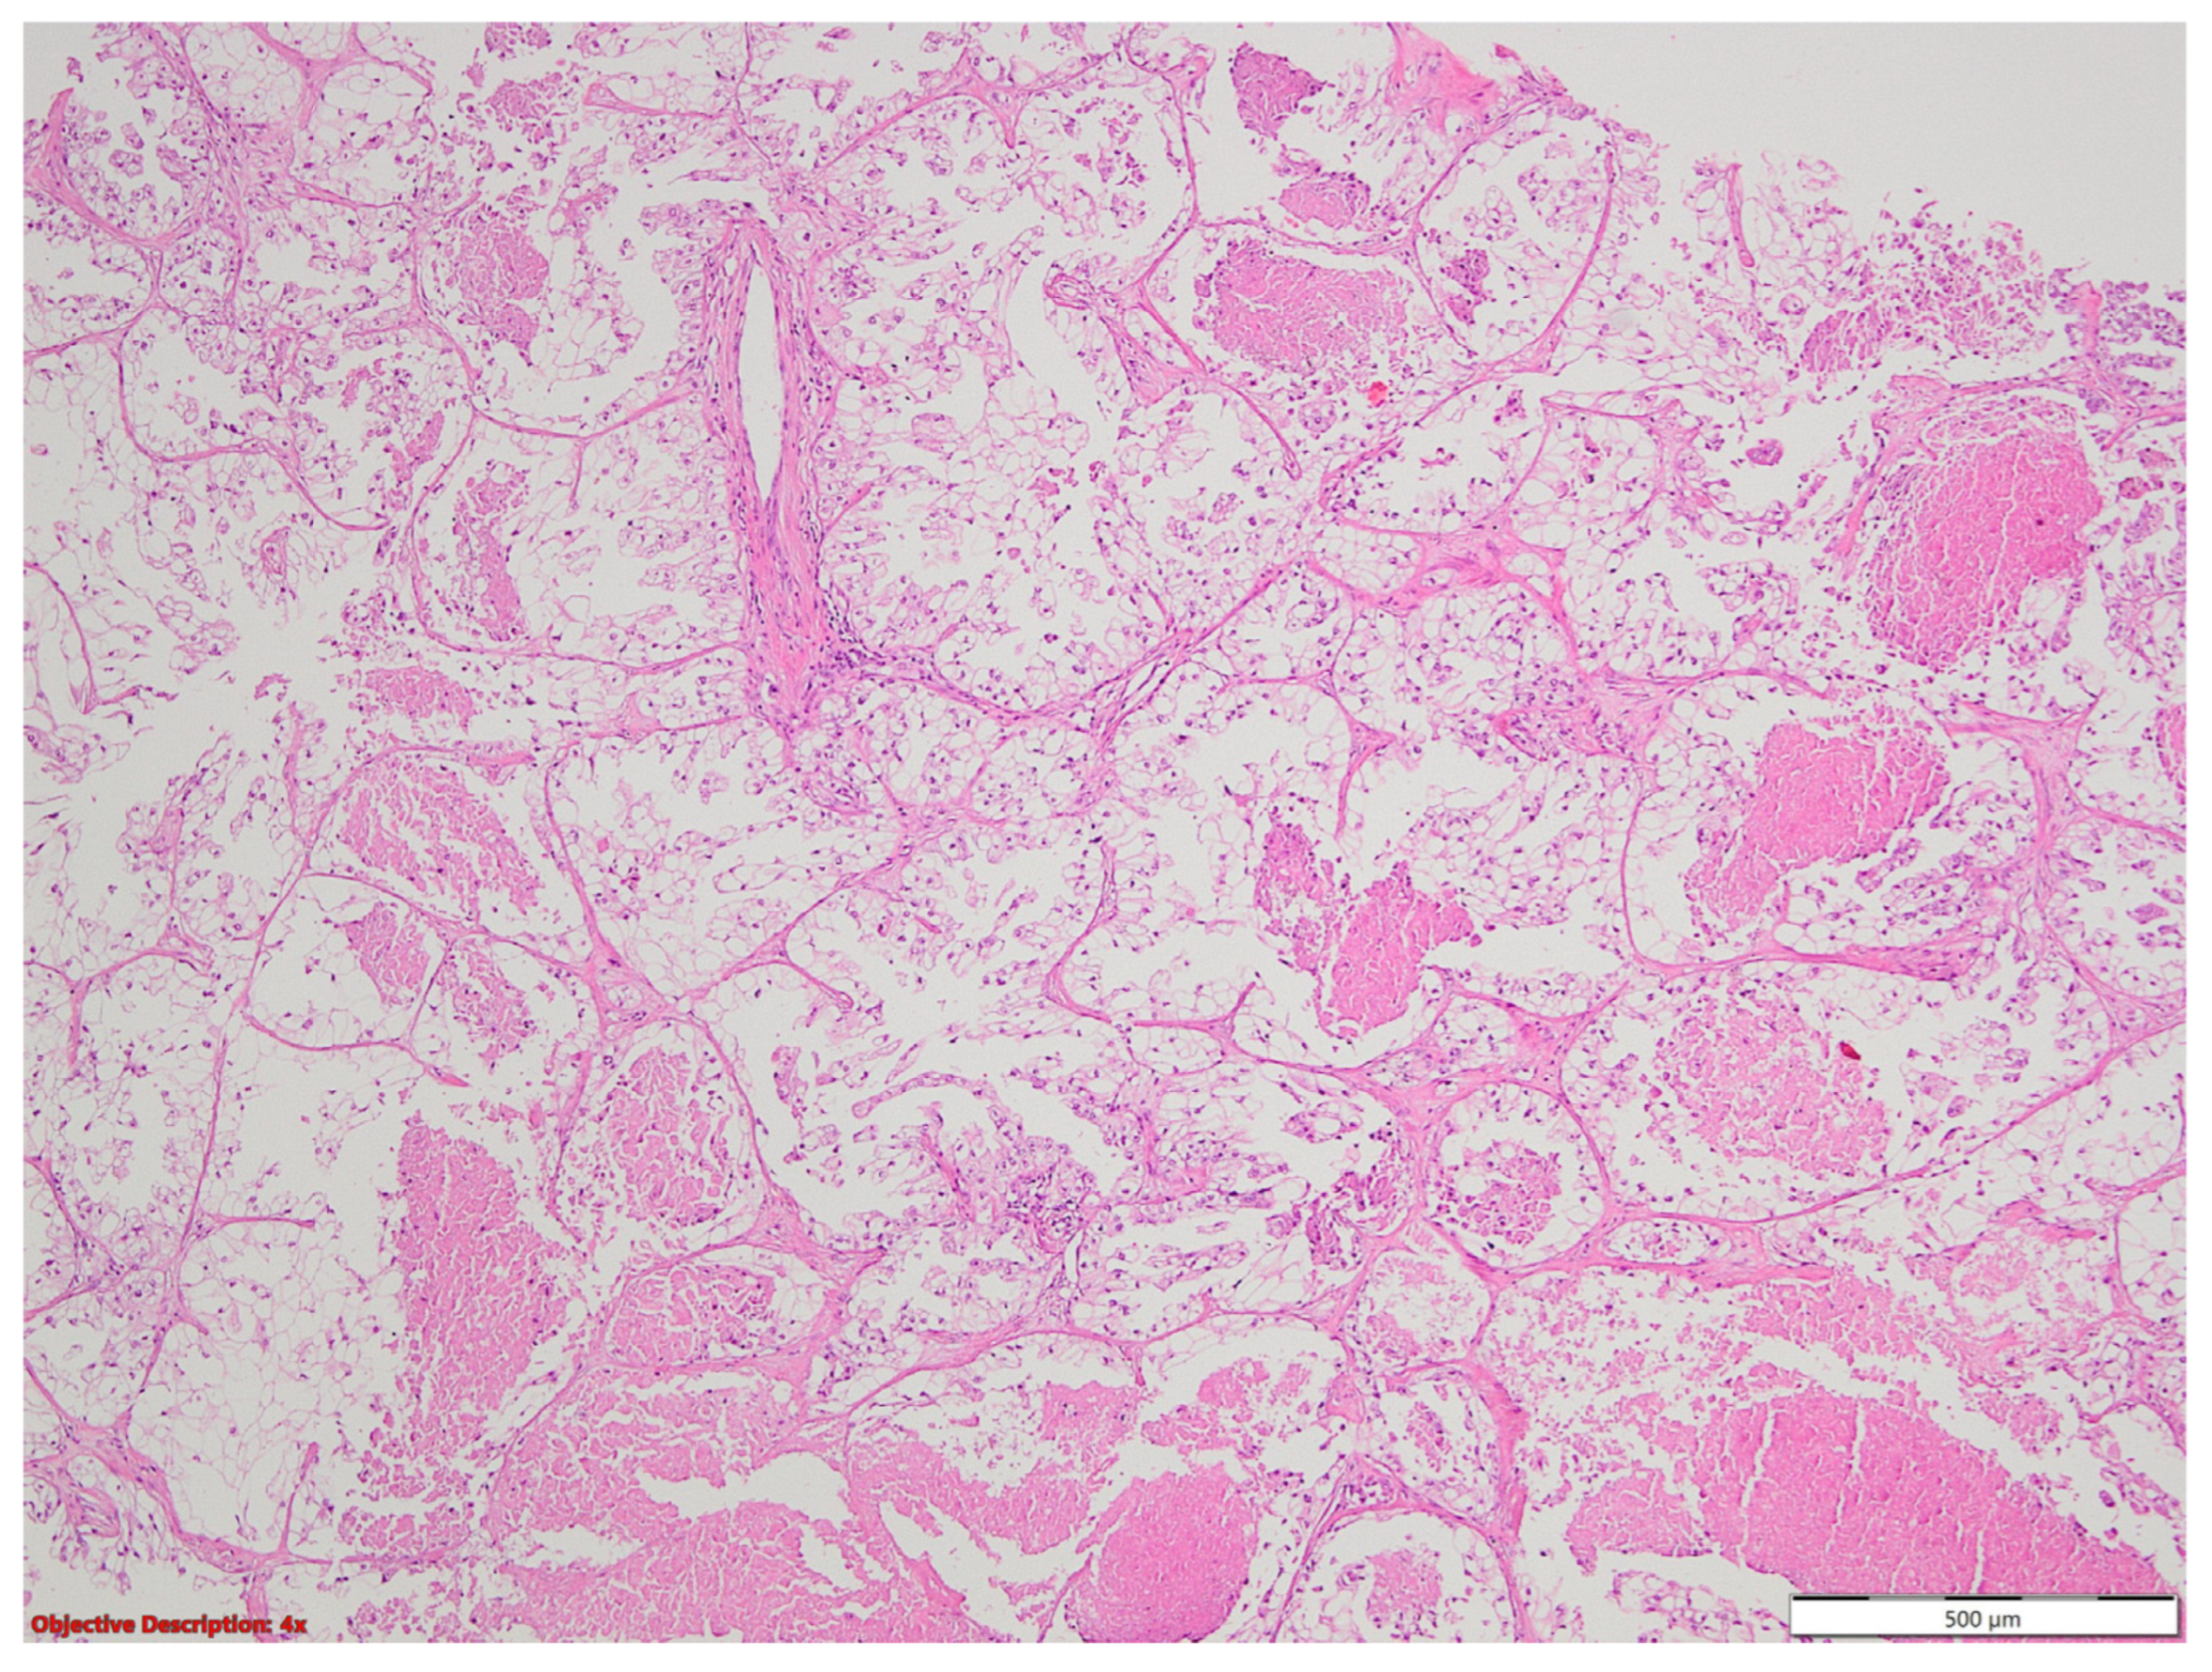

3.1. Case No. 1

3.2. Case No. 2

3.3. Case No. 3

3.4. Case No. 4